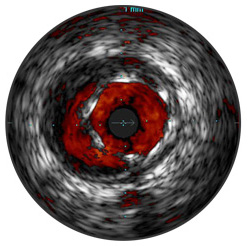

ChromaFlo est disponible sur le système intégré Philips Volcano Core et sur les systèmes Core Mobile, s5 et s5i. Elle permet d’évaluer facilement l’apposition du stent, la dimension de la lumière et autres. L’imagerie échographique ChromaFlo visualise le débit sanguin en rouge par simple pression d’une touche.

ChromaFlo est adaptée aux vaisseaux périphériques et coronaires, y compris l’artère coronaire gauche principale, les bifurcations, l’artère fémorale superficielle et l’artère iliaque. Conçue pour visualiser instantanément la dimension de la lumière et l’apposition du stent, elle aide à identifier les branches, dissections de paroi et thrombus ainsi que la distribution de la plaque au niveau des bifurcations. ChromaFlo est compatible avec les cathéters numériques pour échographie intravasculaire plug-and-play Philips Volcano Eagle Eye Platinum et les cathéters Visions PV 018 et 014.

ChromaFlo visualise le débit sanguin en rouge afin d’identifier :

L’imagerie échographique ChromaFlo est automatiquement enregistrée comme échographie intravasculaire en nuances de gris, permettant l’observation complète du volume de la plaque, du calcium et de la paroi vasculaire.